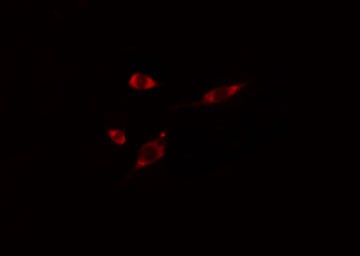

IF (Immunofluorescence)

(AAA325380 staining HT29 cells by IF/ICC. The sample were fixed with PFA and permeabilized in 0.1% Triton X-100, then blocked in 10% serum for 45 minutes at 25 degree C. The primary antibody was diluted at 1/200 and incubated with the sample for 1 hour at 37 degree C. An Alexa Fluor 594 conjugated goat anti-rabbit IgG (H+L) antibody, diluted at 1/600, was used as secondary antibody.)